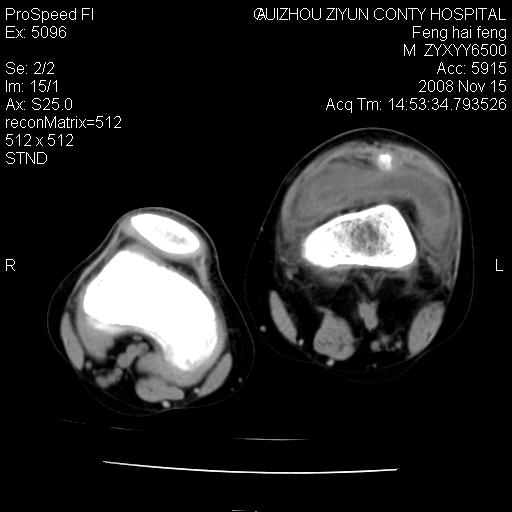

标题: CT16656:M 14Y 左膝关节肿胀一年余。其余病史不详。 [打印本页]

标题: CT16656:M 14Y 左膝关节肿胀一年余。其余病史不详。

考虑左侧髌骨结核;左膝关节滑膜肿胀、增厚,关节囊积液。

左膝滑膜型关节结核可能性大!支持!滑膜型关节结核主要ct表现:关节囊肿胀,积液,关节面见小破坏灶,并见点状死骨!

左膝滑膜型关节结核可能性大!支持!滑膜型关节结核主要ct表现:关节囊肿胀,积液,关节面见小破坏灶,并见点状死骨

好大的左腿!考虑左侧髌骨结核,左膝关节滑膜肿胀、增厚,关节囊积液。

左侧髌骨结核;左膝关节滑膜肿胀、增厚,关节囊积液